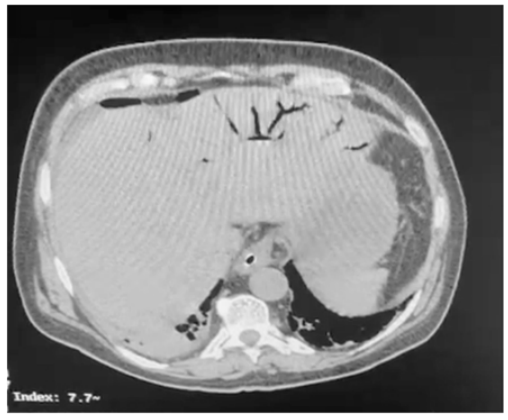

Um paciente de oitenta anos de idade, já com grau de perda de funcionalidade, com períodos de esquecimento, chegou ao pronto-socorro com queda importante do estado geral, com poucas informações objetivas, porém com dor ao exame físico de abdômen. Difícil interpretação dos sinais de irritação peritoneal. Realizou a tomografia abaixo.

A principal causa desse achado é o(a)